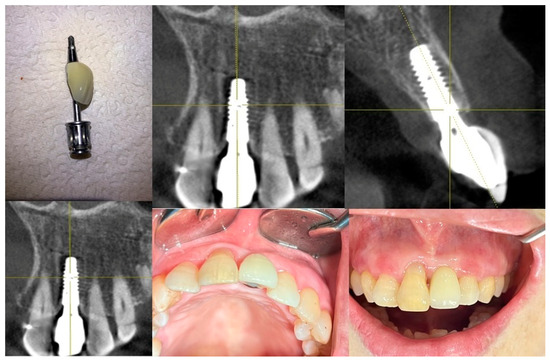

Figure 11 illustrates the step-by-step process of integrating pre-fabricated abutments with subcrestally placed healing abutments and the corresponding biological response of peri-implant soft tissue.

Figure 11.

Procedural steps for matching ready-made abutments with subcrestally placed healing abutments. The upper images include X-rays and clinical photographs, illustrating the process of matching ready-made abutments with subcrestally placed healing abutments. The lower images highlight the transitional zone (TZ) and subcrestal zone (SZ), showing their structural and functional differences. The TZ appears pink and elastic, while the SZ is paler and less elastic. Notably, the SZ forms after using a matching healing abutment due to its proximity to the adjacent subcrestal bone. Despite its thin structure, the SZ remains functional and stable, possibly due to its protected position beneath the TZ.

In the upper images, both X-ray and clinical photographs capture the procedural workflow involved in this process. These images demonstrate how ready-made abutments are carefully matched with subcrestally placed implants. The application of healing abutments plays a crucial role in shaping peri-implant soft tissue, ensuring a well-adapted emergence profile that facilitates long-term soft tissue stability.

The lower images provide a closer look at the peri-implant soft tissue structure following this process. Two distinct zones can be observed: the transitional zone (TZ) and the subcrestal zone (SZ). The TZ appears pink and elastic, indicating its dynamic adaptation to the implant’s emergence profile. In contrast, the SZ is paler and less elastic, positioned closer to the crestal bone, where it serves a more structural and stabilizing role. Unlike the TZ, the SZ is not naturally present, but is formed as a result of healing abutment placement, developing due to its proximity to adjacent subcrestal bone.

Despite its thinness, the SZ remains functionally stable, likely benefiting from its deep subcrestal location, where it is protected from excessive mechanical stress. The overlying TZ may further contribute to this protection, reinforcing the structural and biological stability of the peri-implant soft tissue.

This figure underscores the importance of healing abutments in peri-implant tissue adaptation, revealing how distinct soft tissue zones develop around implants and contribute to long-term stability and biological integration.